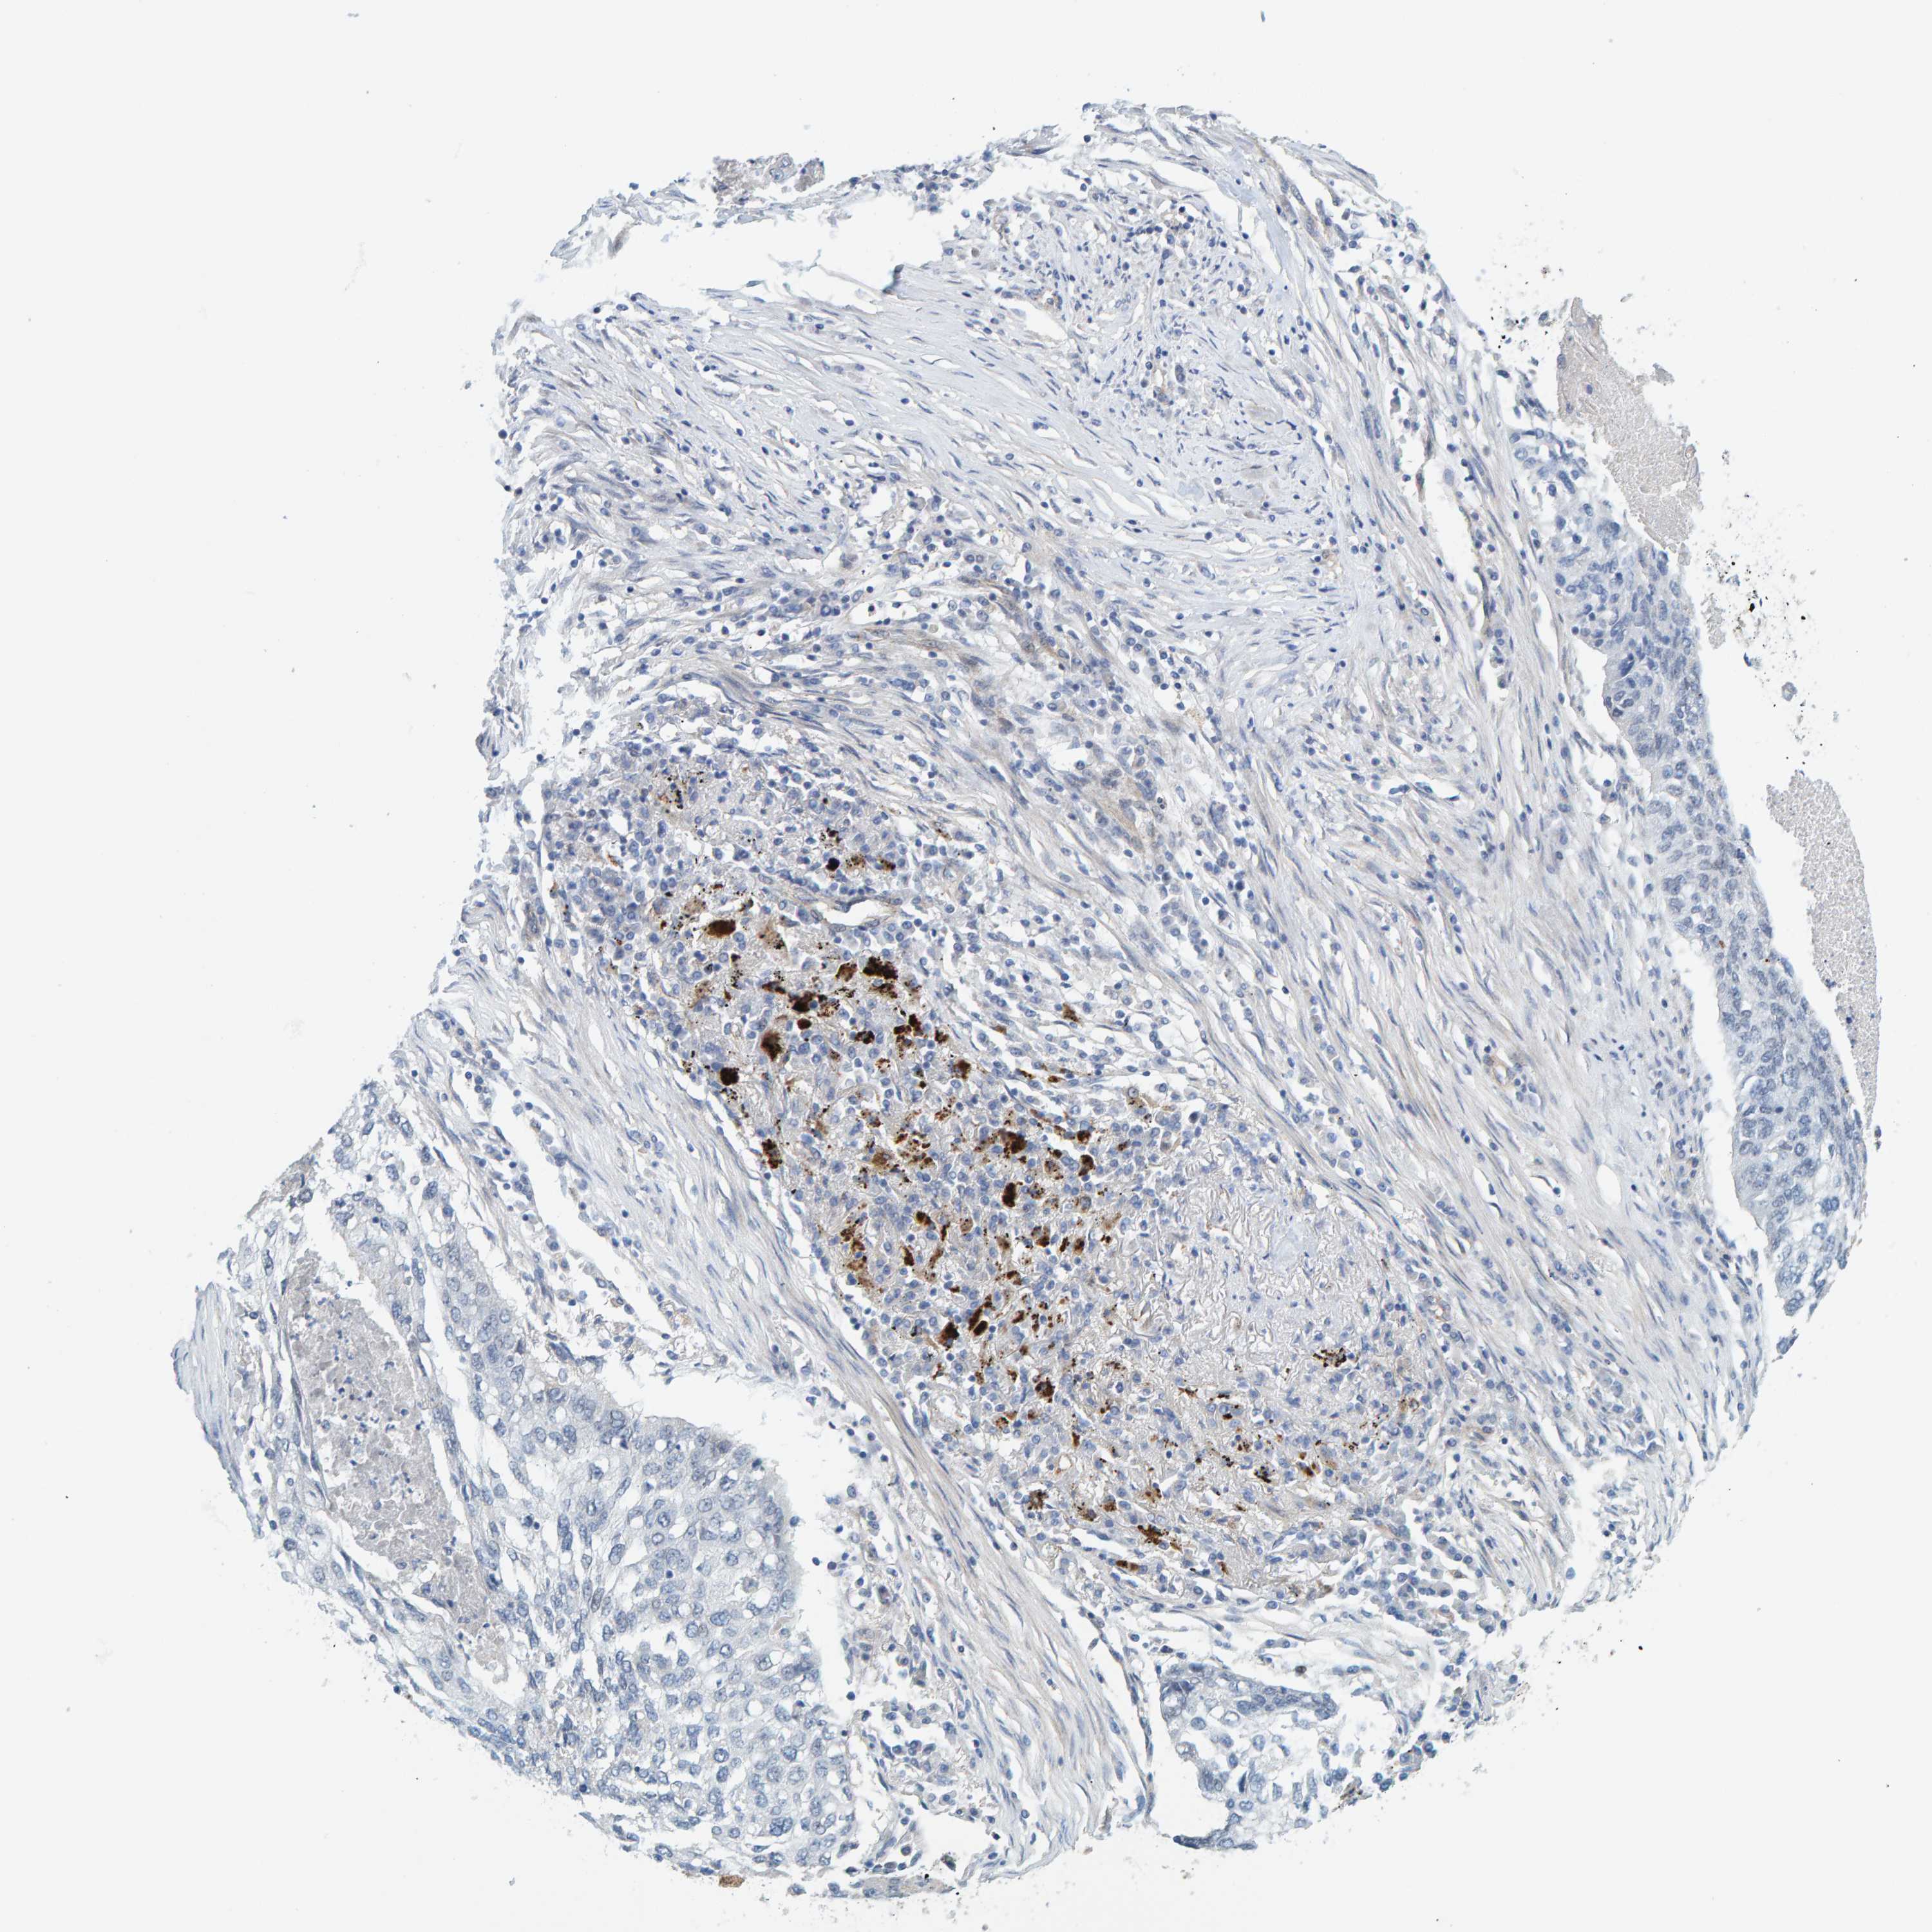

CANCER LUNG CANCER Show tissue menu

LUAD TCGA LUAD VALIDATION LUSC TCGA LUSC VALIDATION PROTEIN LUAD CPTAC PROTEIN LUSC CPTAC PROTEIN EXPRESSION

ANTIBODIES

AND

VALIDATION